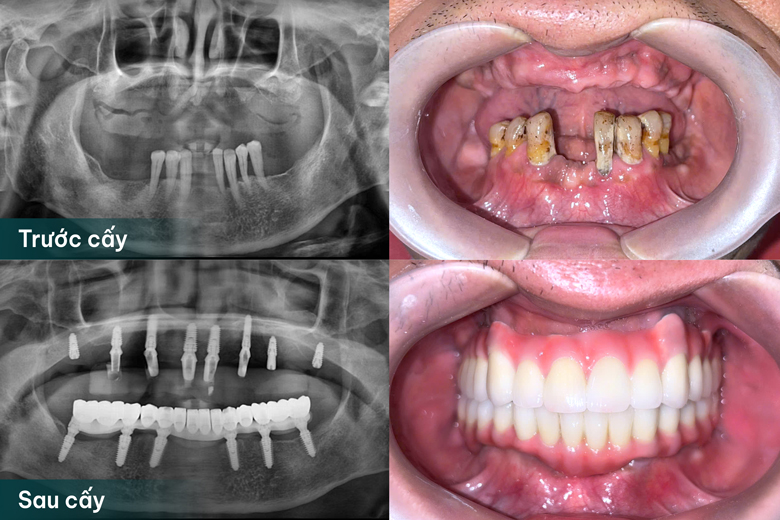

Tình trạng răng của chú Luyện trước và sau cấy ghép Implant tại MauLux Dental